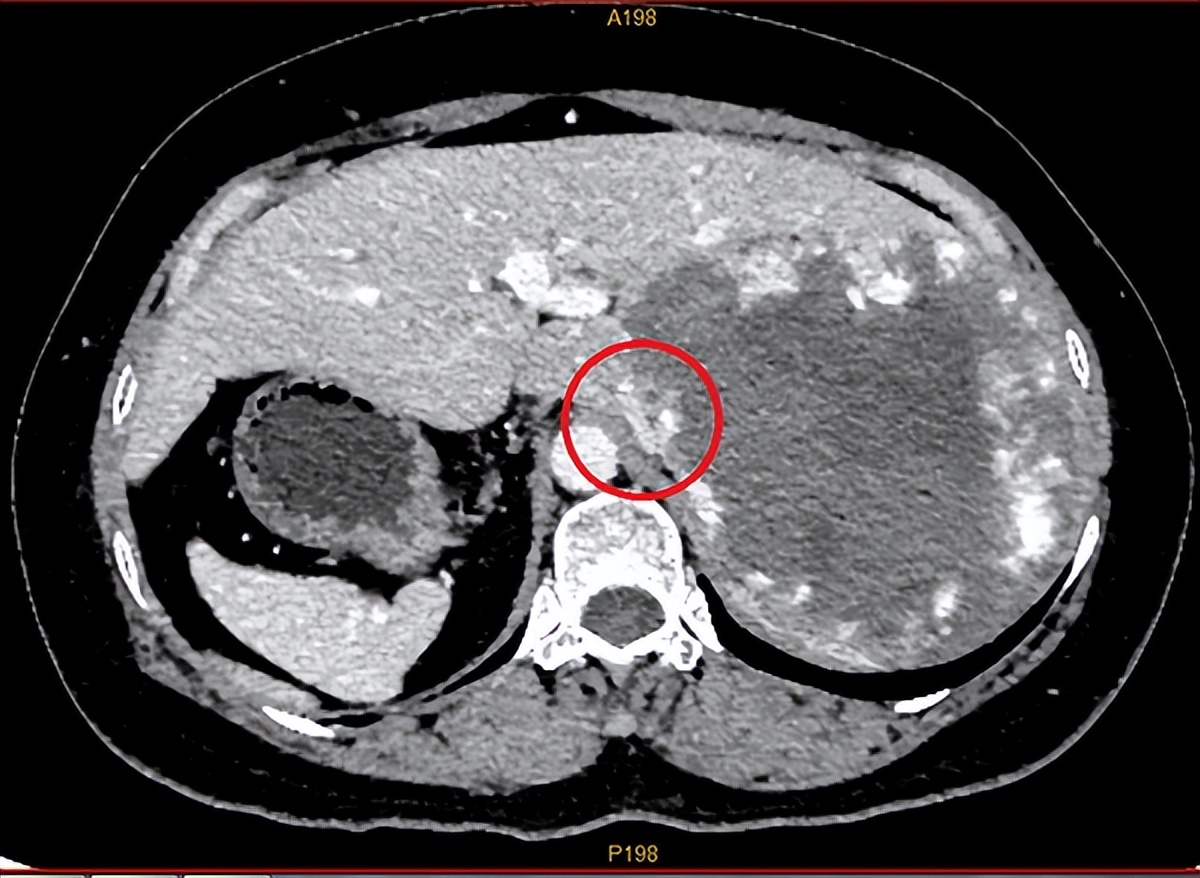

近日消息,广西医科大学附属武鸣医院接诊了一位特殊的病人卢女士。她因为上腹不适到医院就医,医生检查后发现卢女士不仅长了一个巨大血管瘤,而且器官内脏还是反着长的!

据医生介绍,卢女士的血管瘤体积巨大,已经占据她整个右肝范围,必须进行手术,但是,血管瘤一旦在术中破裂,止血异常困难,手术可能危及生命。

最终历经5个小时的手术后,医生从卢女士体内切除出一个15 x 14×12厘米的巨大血管瘤,目前,卢女士恢复良好,已顺利出院。

图片来源:广西医科大学附属武鸣医院